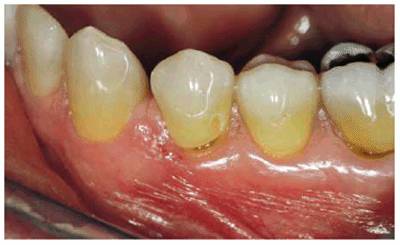

patient (Figures 17-1A to

C

Figure 17-1A to C: These photographs illustrate the complex dental condition of a 71-year-old male: (A) The palatal cervical regions of the maxillary anterior teeth exhibit sharp, wedge-like lesions that are characteristic of abfraction. These areas would be difficult, if not impossible, to have resulted from toothbrush abrasion. (B) The buccal aspects of the maxillary posterior teeth show smooth, concave configurations that are consistent with toothbrush abrasion and/or erosion. (C) The buccal surfaces of the mandibular teeth have lesions that possess components of both abfraction (sharp margins in the occlusal regions) and abrasion (concave geometry and gingival recession in the cervical regions).